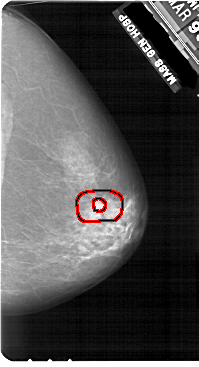

A_1908_1.RIGHT_CC

RIGHT_CC LINES 5491 PIXELS_PER_LINE 2971 BITS_PER_PIXEL 12 RESOLUTION 43.5 OVERLAY

FILE: A_1908_1.RIGHT_CC.OVERLAY

TOTAL_ABNORMALITIES 1

ABNORMALITY 1

LESION_TYPE MASS SHAPE IRREGULAR MARGINS SPICULATED

ASSESSMENT 5

SUBTLETY 4

PATHOLOGY MALIGNANT

TOTAL_OUTLINES 2

BOUNDARY

CORE